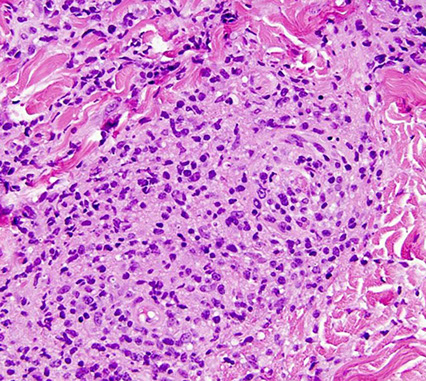

Histo: dense mononuclear infiltrate c foamy histiocytes and formation of Touton GCs

- overlying dermis looks flattened; inc eos common

IHC: (+) CD56 / HAM65, S100

JXG